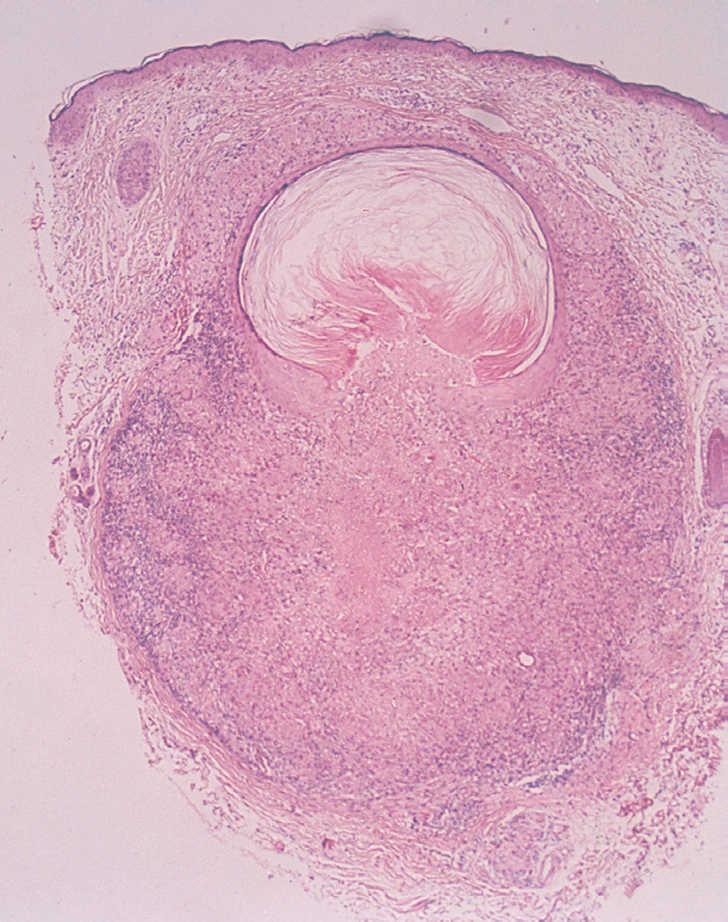

Los estudios de bioquímica sanguínea, hemograma y radiografía de tórax estaban dentro de la normalidad. La prueba de Mantoux fue negativa. El estudio histológico, que incluía los dos tipos de lesiones descritas, mostraba un granuloma tipo tuberculoide, bien definido, con necrosis central y un infiltrado de linfocitos alrededor de un pequeño quiste epidérmico roto. La necrosis caseosa estaba en contacto con el contenido del quiste (fig. 3). Se realizó otra biopsia de una pápula eritematosa, donde se observaba de forma aislada un granuloma tipo tuberculoide con necrosis central (fig. 4). La tinción de Ziehl fue negativa. Tras la exploración física, el estudio histológico y las pruebas complementarias para excluir otras enfermedades granulomatosas, se estableció el diagnóstico de LMDF.

Fig. 4.--Biopsia de una pápula eritematosa. Granuloma tuberculoide aislado con necrosis. (Hematoxilina y eosina, x4.)